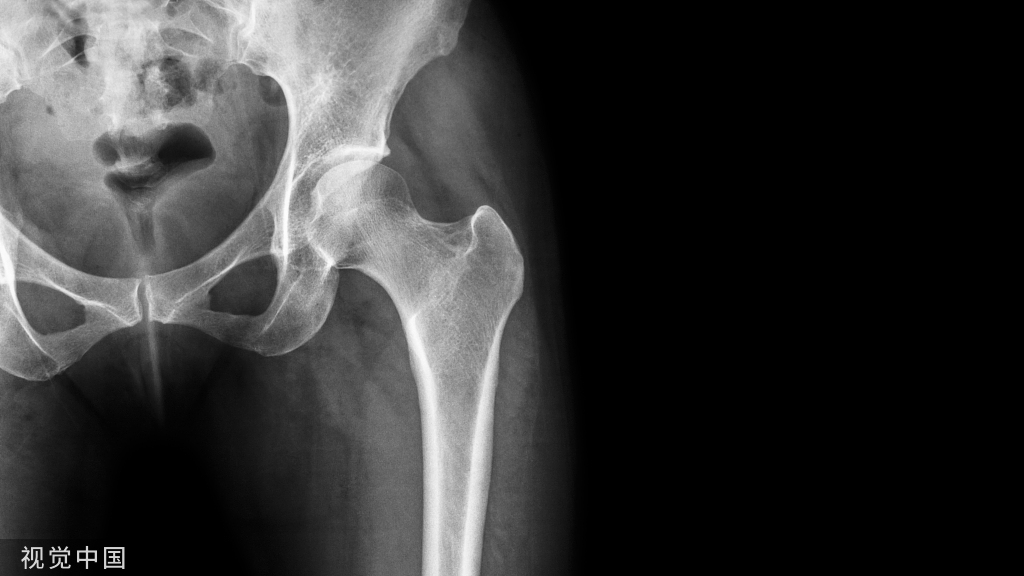

X线平片(首选方法):

- 骨盆正位片:尾骨尖端指向耻骨联合,且二者之间的距离是1~2 cm 。

- 能显示股骨近端、髋臼盂缘的骨性解剖异常。

X线表现

1、凸轮撞击型

直接表现:

- 股骨头颈联合处前上缘骨性突起:“ 枪柄样” 畸形。

- 非圆形的股骨头。

- 股骨头颈偏心距减小。

- α角增大。

凸轮撞击型FAI▼

- 股骨头颈间的凹陷不足,伴局部的骨质增生。

- 股骨头颈的“ 枪柄样” 畸形。